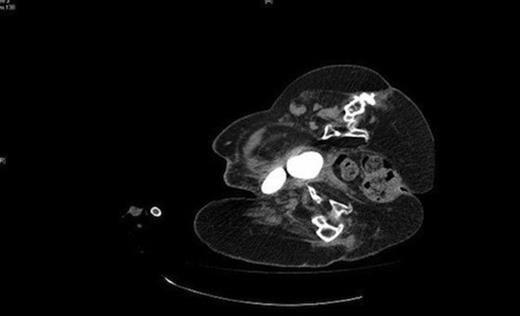

A urology opinion was sought, initially, with regard to management of the suprapubic catheter. On closer examination, urine was noted to be leaking not from the suprapubic site but around the calcified mass in the right groin and a diagnosis of vesicocutaneous fistula was made. Her radiographs demonstrated two urinary calculi (Fig 1) and she went on to have an abdominal computed topography scan (Fig 2 ) which confirmed the diagnosis of a vesicocutaneous fistula.

CT demonstrating the two bladder calculi pointing towards the right groin